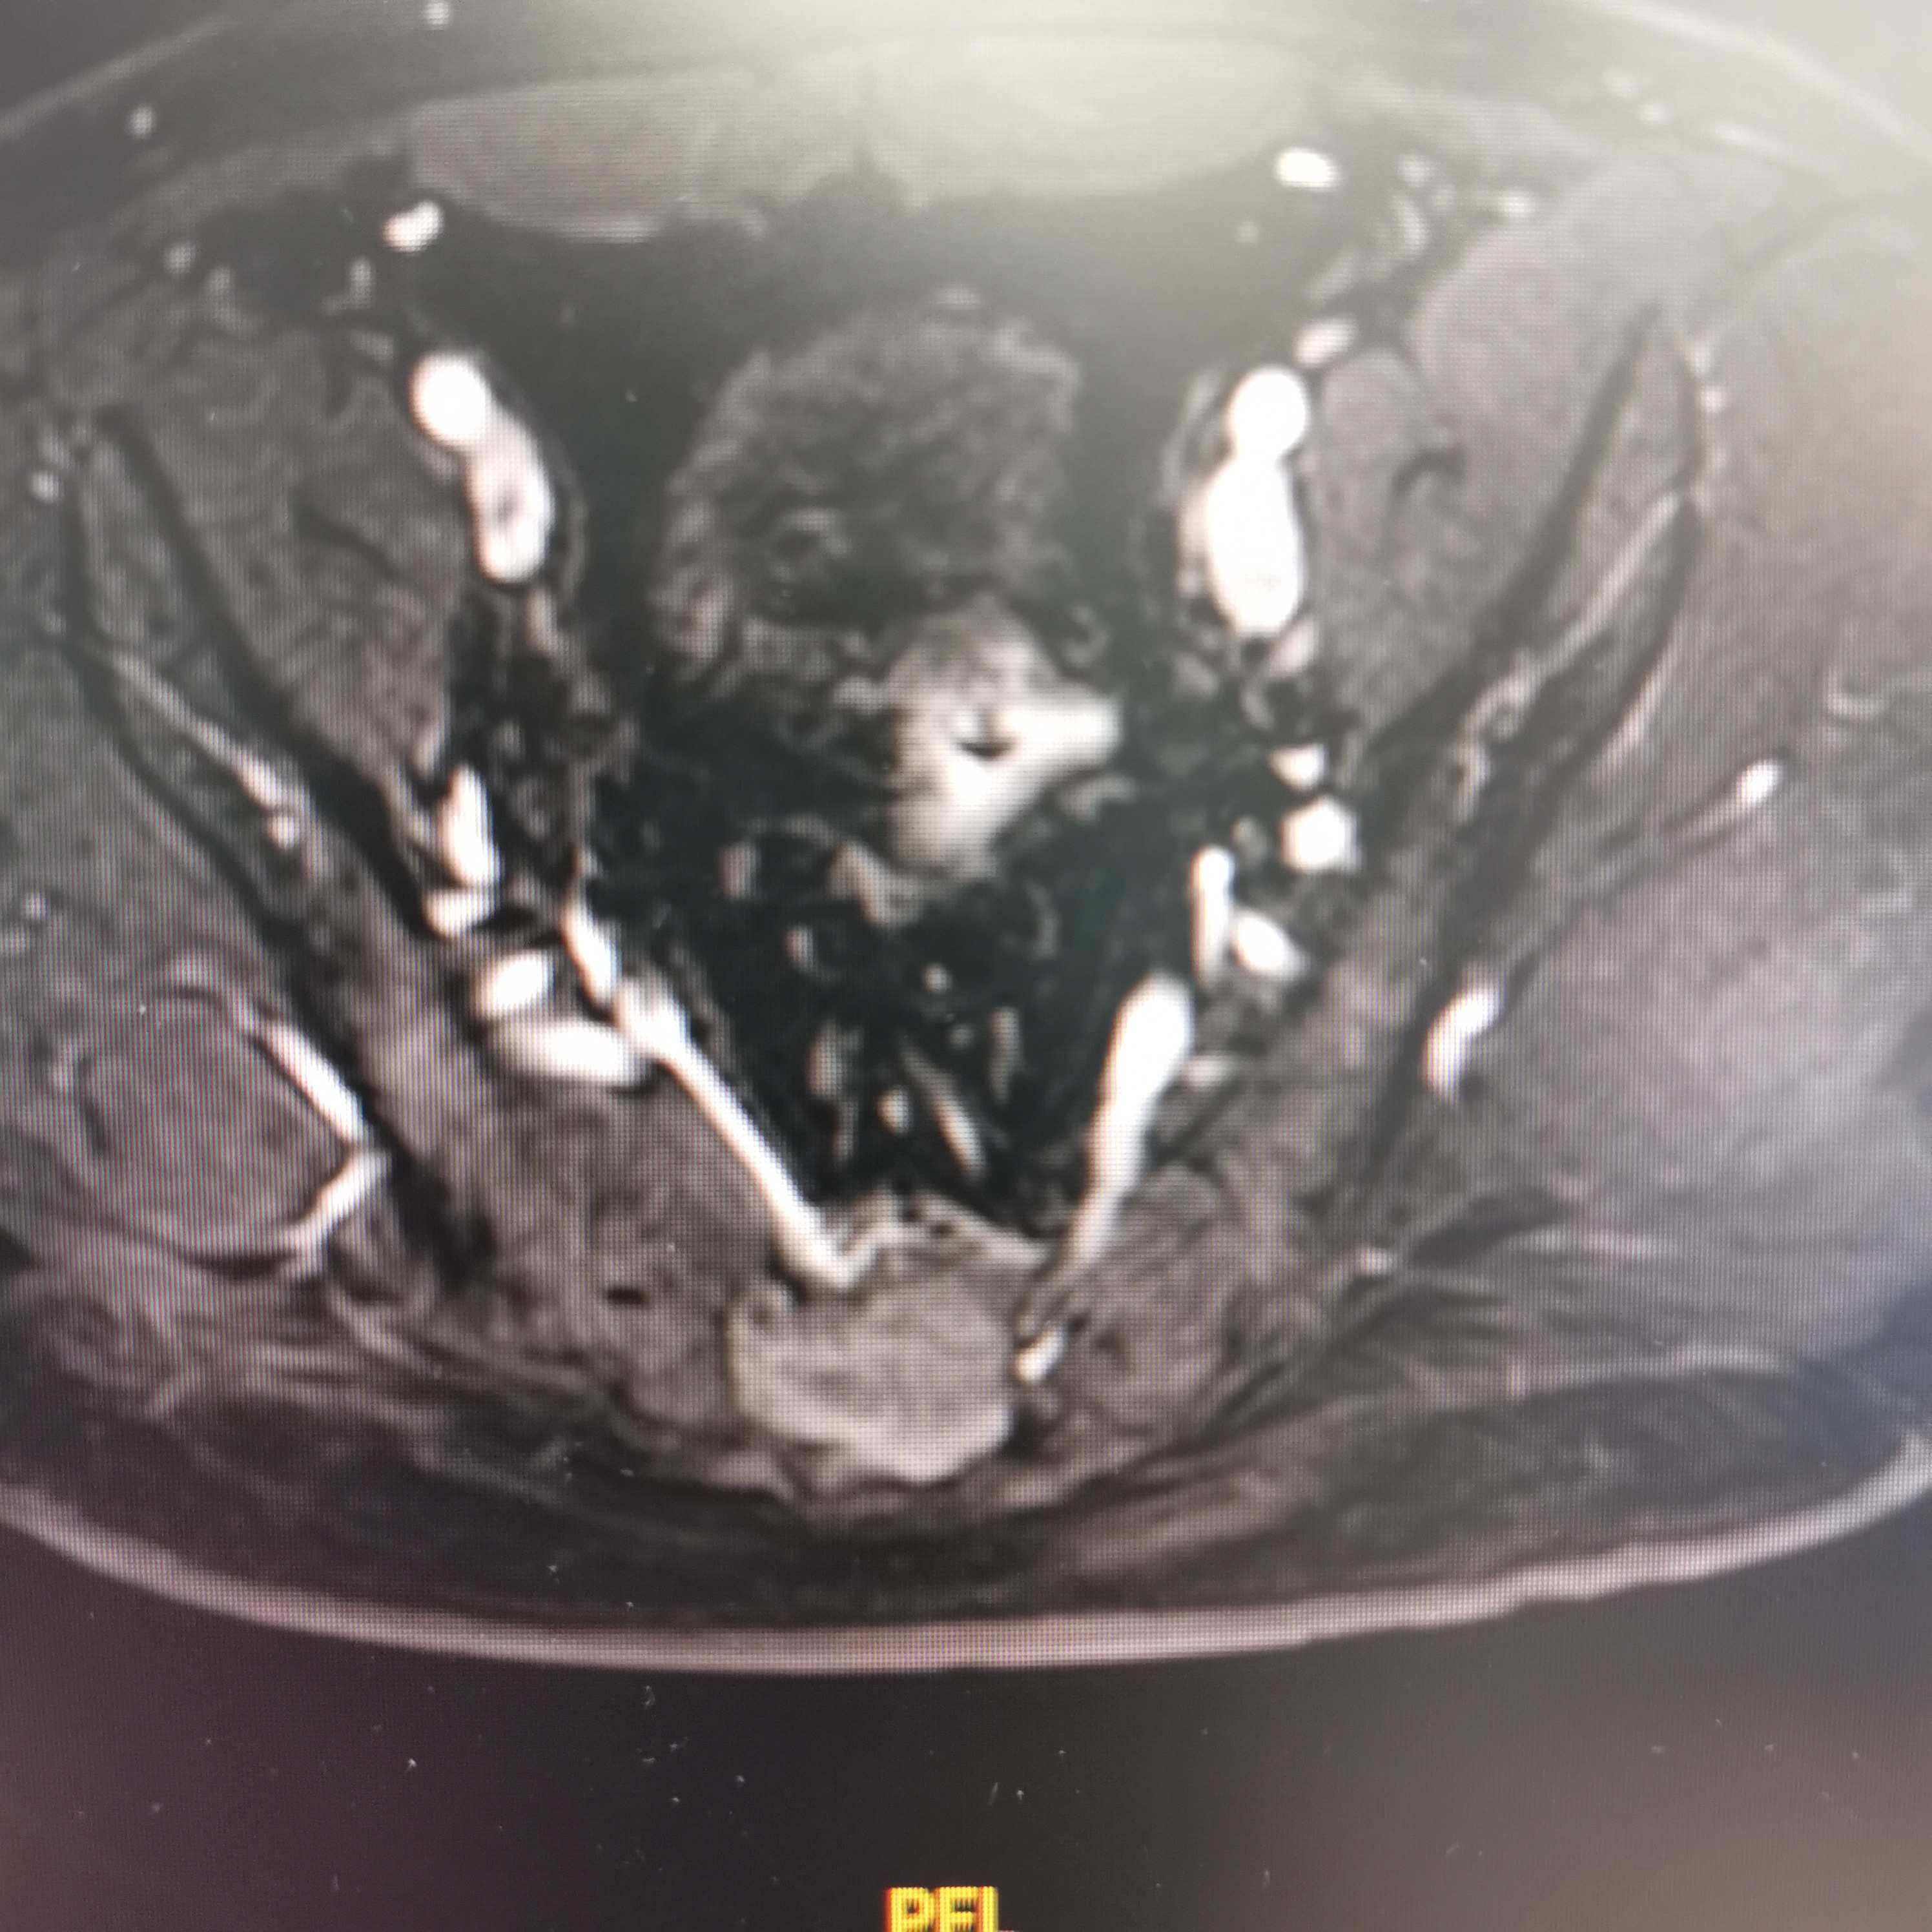

骶椎神经鞘瘤